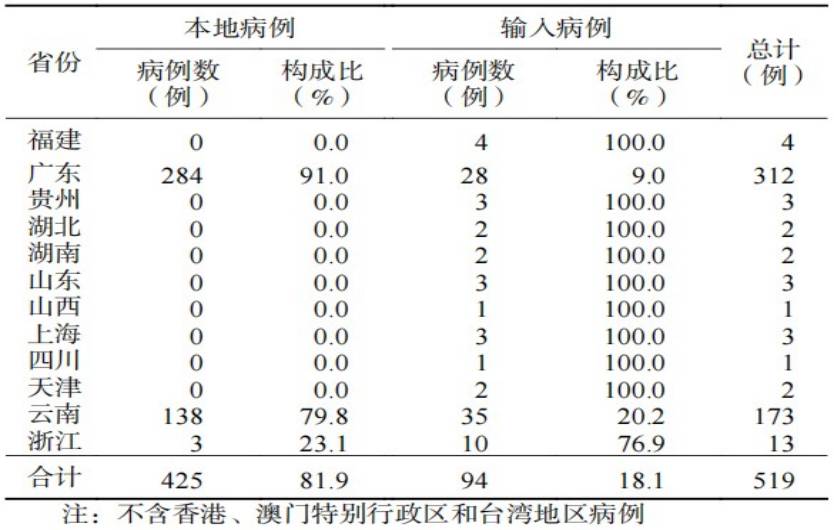

登革熱在全球存在媒介伊蚊分布的熱帶、亞熱帶地區(qū)廣泛流行,累及全球100多個國家和地區(qū)。我國雖尚未形成穩(wěn)定的登革熱本地傳播疫源地,但輸入性病例常年可見。廣東、云南、福建、浙江、廣西、海南等多個省份曾多次發(fā)生輸入引發(fā)的本地傳播登革熱疫情,夏秋季高發(fā),各年齡段人群均可發(fā)病,以青壯年為主。

2010-2024年中國登革熱病例報告數(shù)

注:不含香港、澳門特別行政區(qū)和臺灣省病例